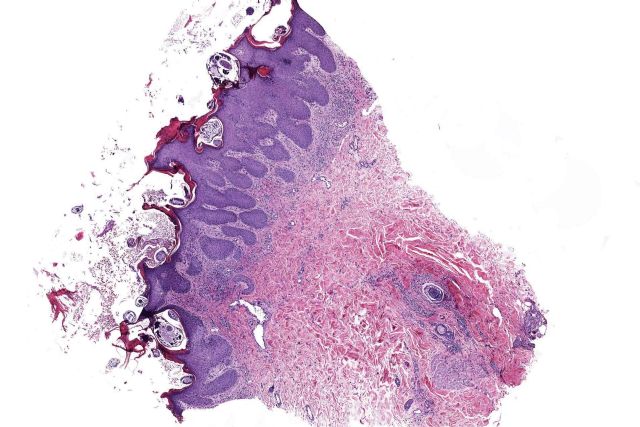

Dentro del equipamiento, cuentan con escáneres para la digitalización de muestras citológicas e histológicas, de tal manera que aquellos clientes que lo requieran, pueden recibir las imágenes digitales de sus muestras; de igual forma, se pueden recibir imágenes digitalizadas para su diagnóstico. Estos informes se pueden enviar por el medio que el cliente elija, incluyendo al sistema de información del cliente.